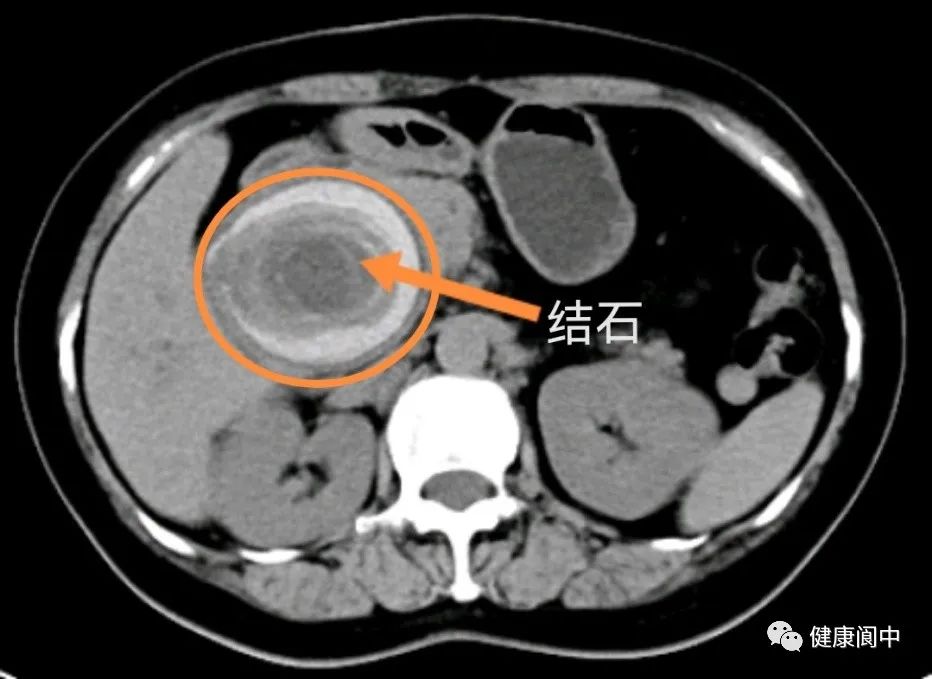

家住阆中双龙镇的秦女士最近半年反复被肚子疼所困扰,起初自以为是胃病,自己在家“中药”“西药”轮着吃,腹痛均不见减轻,后来到阆中市人民医院检查。检查结果把她本人和医生都吓了一大跳,胆管里面竟然有一个鸵鸟蛋大的石头。正常胆管只有6mm左右粗,然而,她胆管内石头却有约7cm粗。如此大的胆管结石,目前国内外几无报道。

巨大的结石以及长期的慢性炎症刺激对周围脏器及肝门大血管挤压导致粘连及解剖异常,加之患者曾做过开刀胆囊切除手术,给本次手术带来巨大的难度和风险。经过详细的术前讨论和规划,由黎万里副主任医师和龚文主治医师成功为患者行了腹腔粘连松解+胆管切开取石+胆道镜检查+肝外胆管切除+肝门胆管整形+胆肠Roux-en-Y吻合术,手术历时4小时,出血仅50ml。术后在医护团队精心照顾下,患者恢复顺利,目前已出院。